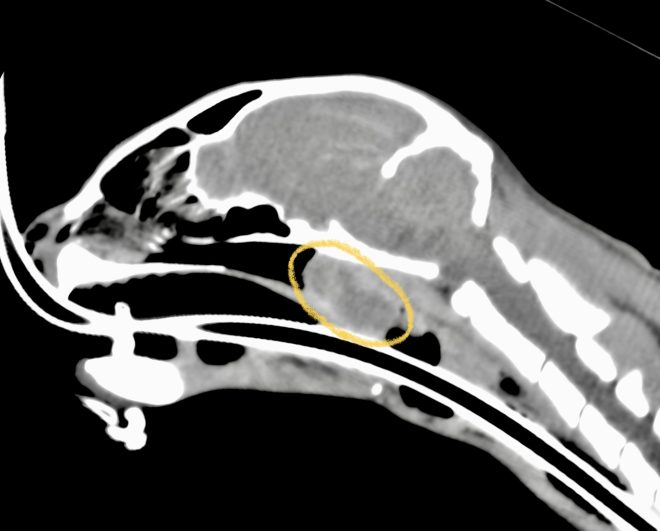

CT検査では、鼻咽頭に左の耳管から続く腫瘤(オレンジ丸)がほぼ完全に鼻咽頭を閉塞していました。また、左の中耳にも病変(青矢印)を認めました。